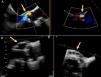

A 72-year old woman with a history of mechanical aortic prosthesis since 2010 and early infective prosthetic endocarditis (medical treatment) was hospitalized for acute heart failure in February 2015. Transesophageal echocardiography showed a severe paravalvular leak in the posterior portion of the aortic prosthesis (Figure 1A, arrow) and a pseudoaneurysm with fistulization to the left ventricle (LV) and aorta (Figure 1B, arrow), moderate mitral regurgitation and mild LV systolic dysfunction. Surgery was considered high risk and percutaneous closure of the paravalvular leak was attempted. The procedure was guided by fluoroscopy and transesophageal echocardiography. After confirming the stability of the device (Amplatzer® Vascular Plug II 12 mm/9 mm) and reduction of the paravalvular leak without functional compromise of the mechanical prosthesis (Figures 2A and 2B, arrow), the device was released. Minutes after deployment, the device migrated into the LV (Figure 3A, arrow and Supplementary data online, Movie S1). The device could not be retrieved (Figure 3B, arrow). Echocardiography images showed the device lodged beneath the posterior mitral leaflet, entrapped in the subvalvular mitral apparatus, with no significant compromise of mitral valve function (Figures 4A, arrow and 4B, arrow and Supplementary data online, Movie S2). Follow-up echocardiographies showed the device still in the same position. The patient died of sepsis due to a Clostridium difficile infection 58 days after admission (one month after the procedure). This case illustrates a rare and dramatic complication of percutaneous leak closure, but without significant hemodynamic impact on mitral valve and LV function.